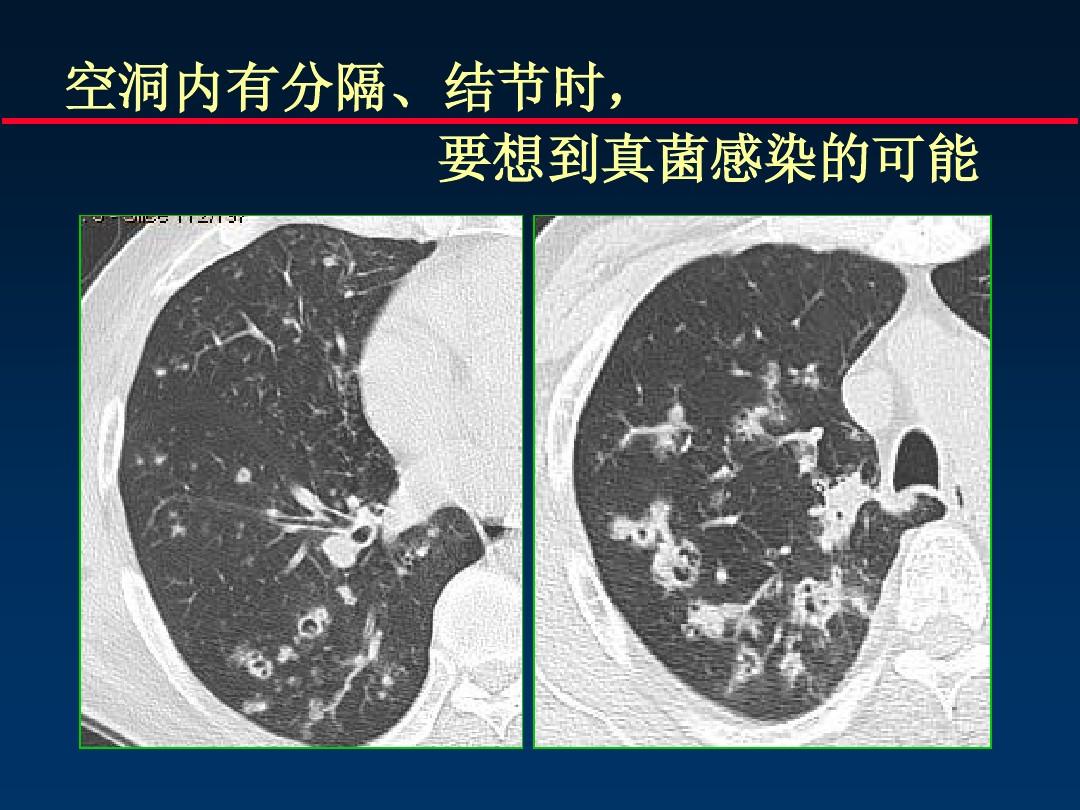

有一种真菌专门在肺部原有疾病产生的空洞里长小球